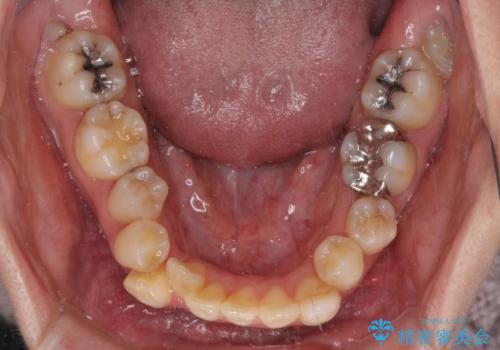

- 前歯の八重歯やデコボコを気にして来院された患者様です。

口元の突出感はありませんが、前歯の重なりが著しいため、目立ちにくい表側のワイヤー装置にて、上下左右の第一小臼歯4本を抜歯して矯正治療を行うこととしました。